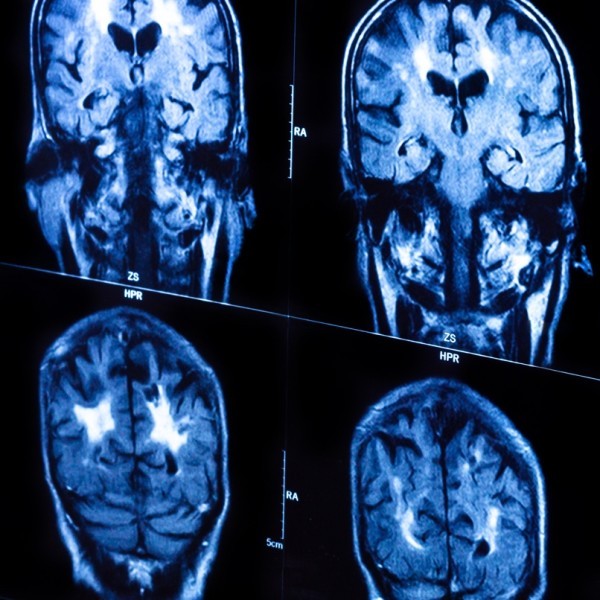

Как известно, самой активной и сложной частью человеческого мозга является его кора. В ходе исследования внутри слоев мозговой коры человека ученые обнаружили более плотную область тканей по сравнению с животными. Наблюдая за тем, как проявляется мозговая деятельность во втором и третьем корковых слоях, было найдено возможное подтверждение того, что некоторые из наших нейронов способны выполнять функции, которые ранее считались для них невозможными.

В своем исследовании команда немецких и греческих ученых попыталась поподробнее изучить запутанные связи между нейронами нашего головного мозга. В результате они пришли к выводу, что отдельные нейроны могут выполнять вычисления, которые ранее считались выполнимыми только сетями нейронов.

По сути, ученые вычислили, что мозг человека способен регулировать амплитуду электрической активности с целью повышения продолжительности и эффективности ее сигналов. Это позволяет индивидуальным нейронам делать больше, нежели просто определять то или иное состояние – осуществлять вычисления на основе XOR (не И или ИЛИ, а исключающее ИЛИ). Ранее данная функция считалась невозможной для выполнения отдельным нейроном.